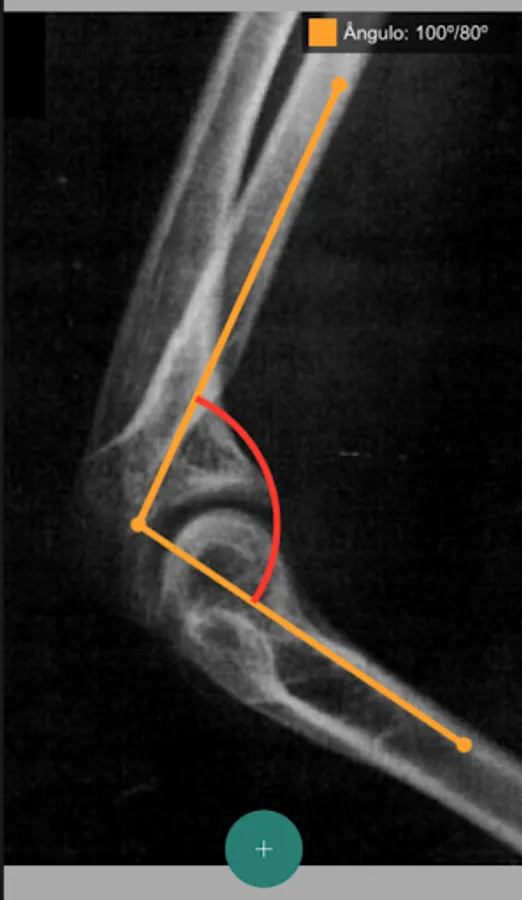

This SBOT App brings together useful tools for the Orthopedist. It allows the consultation, categorization and sharing of TUSS and AMB codes, as well as the drawing of angles on exam and patient images that can also be shared. An initiative of the Young Orthopedist Commission.

SBOT Jovem Screenshots